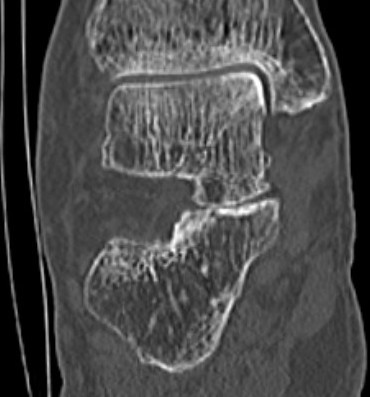

Subluxation of TNJ with advanced STJ OA

TNJ OA with posterior / medial / anterior facet OA of the subtalar joint